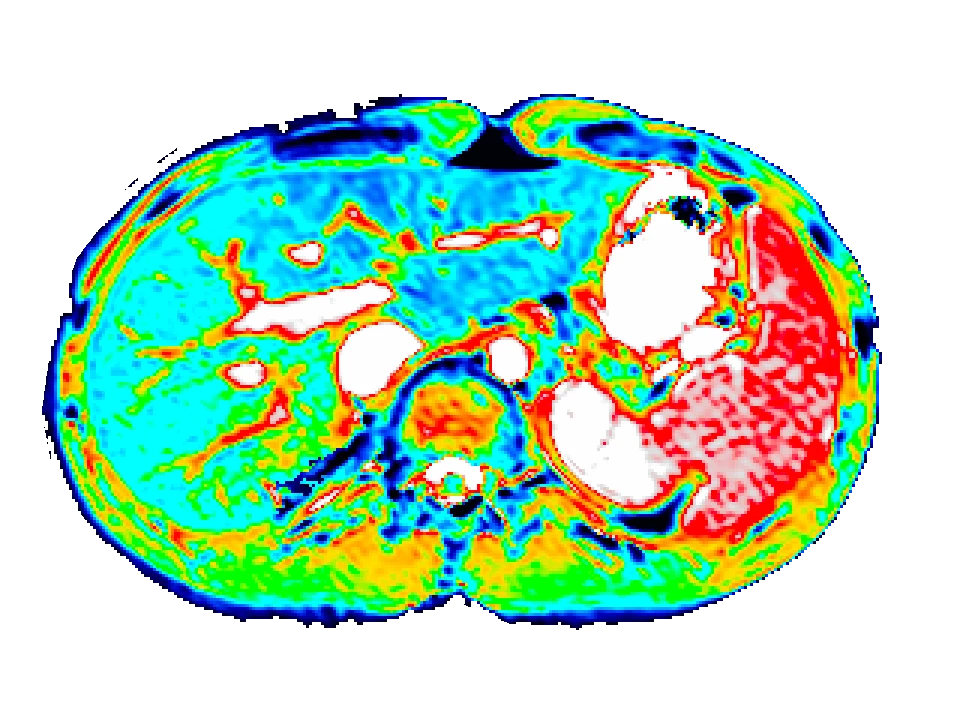

Bioxydyn uses dynamic gadoxetate-enhanced MRI to assess liver transporter function non-invasively. Gadoxetate is taken up by functioning hepatocytes and excreted into bile, allowing MRI to measure key aspects of hepatobiliary transport in vivo. By combining dynamic imaging with quantitative modelling, we can derive biomarkers of hepatocellular uptake and biliary excretion, alongside complementary measures such as relaxation time mapping.

This approach provides functional information that cannot be obtained from standard anatomical imaging or blood measurements alone. It is particularly relevant where changes in liver transport may affect drug exposure, clearance, or tissue accumulation.